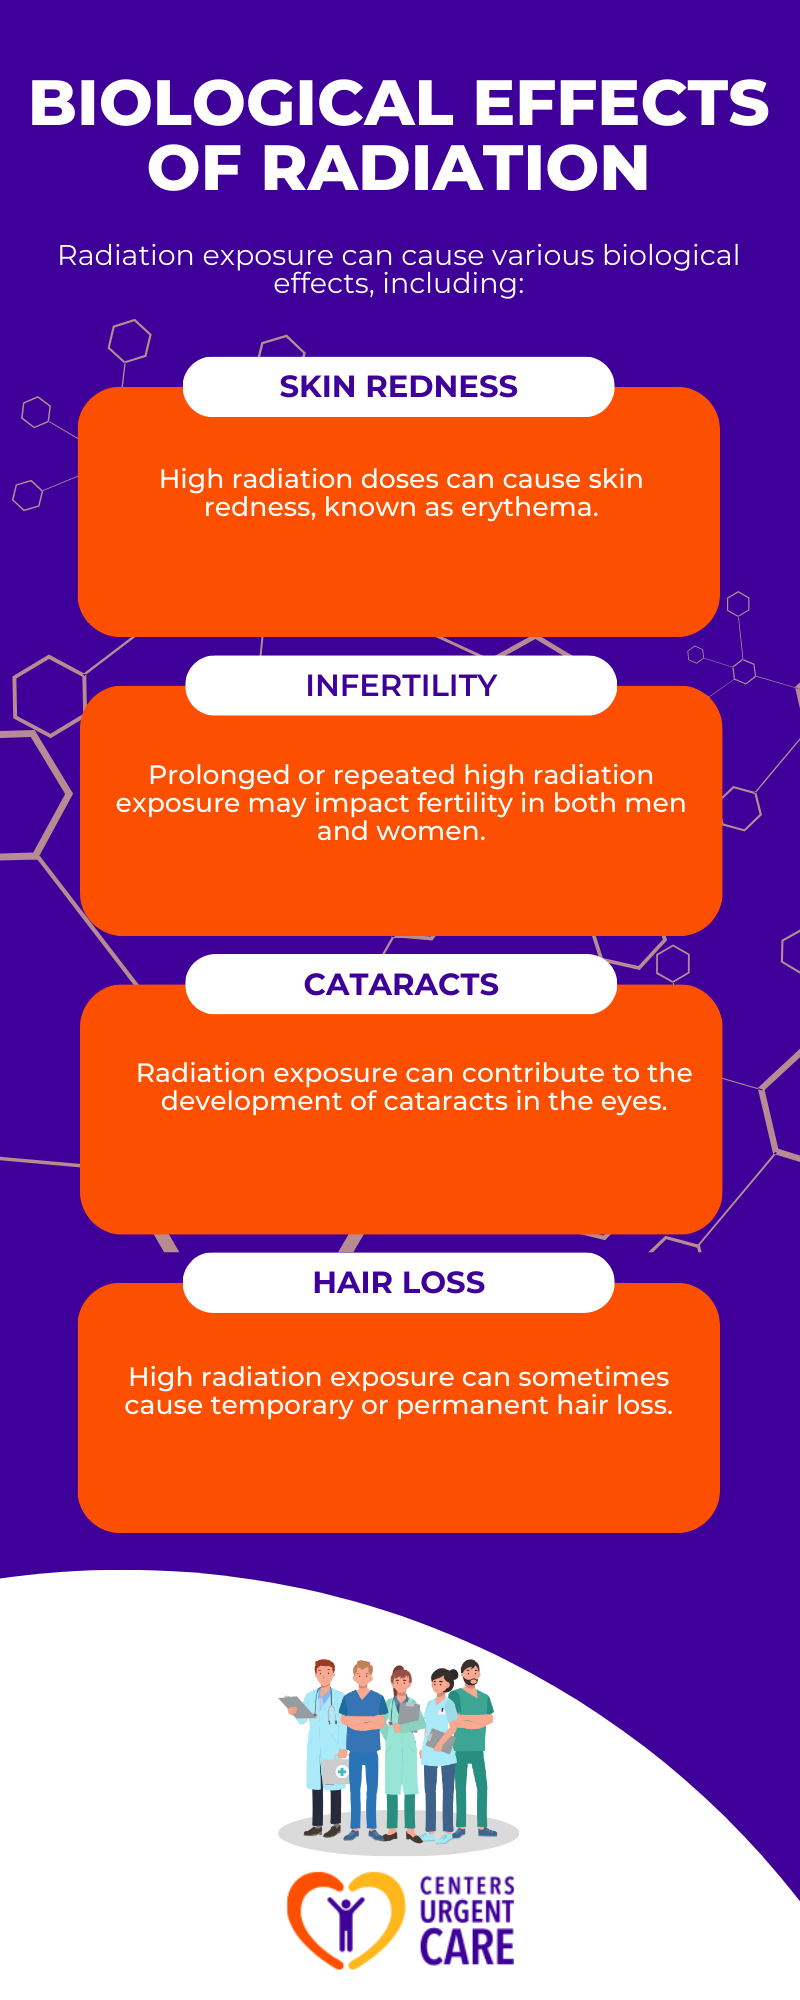

Effects of High Radiation Doses

When considering the effects of high radiation doses from X-ray exposure, it’s important to understand both the biological effects of radiation and the potential adverse effects that individuals may experience.

Potential Adverse Effects

While adverse effects from diagnostic and interventional procedures involving radiation are rare, it’s essential to be aware of the potential risks associated with high radiation doses. Patients undergoing interventional procedures that require fluoroscopy for extended periods, lasting one hour or more, maybe at a slightly higher risk of experiencing radiation-induced skin injuries, such as erythema.

It’s important to note that there are no documented reports of diagnostic and interventional procedures causing infertility or cataracts in patients. However, it’s crucial for healthcare providers to carefully assess the radiation dose levels. Additionally, it’s important to remember that exposure to diagnostic X-rays and nuclear medicine examinations has been linked to a slightly increased risk of cancer.